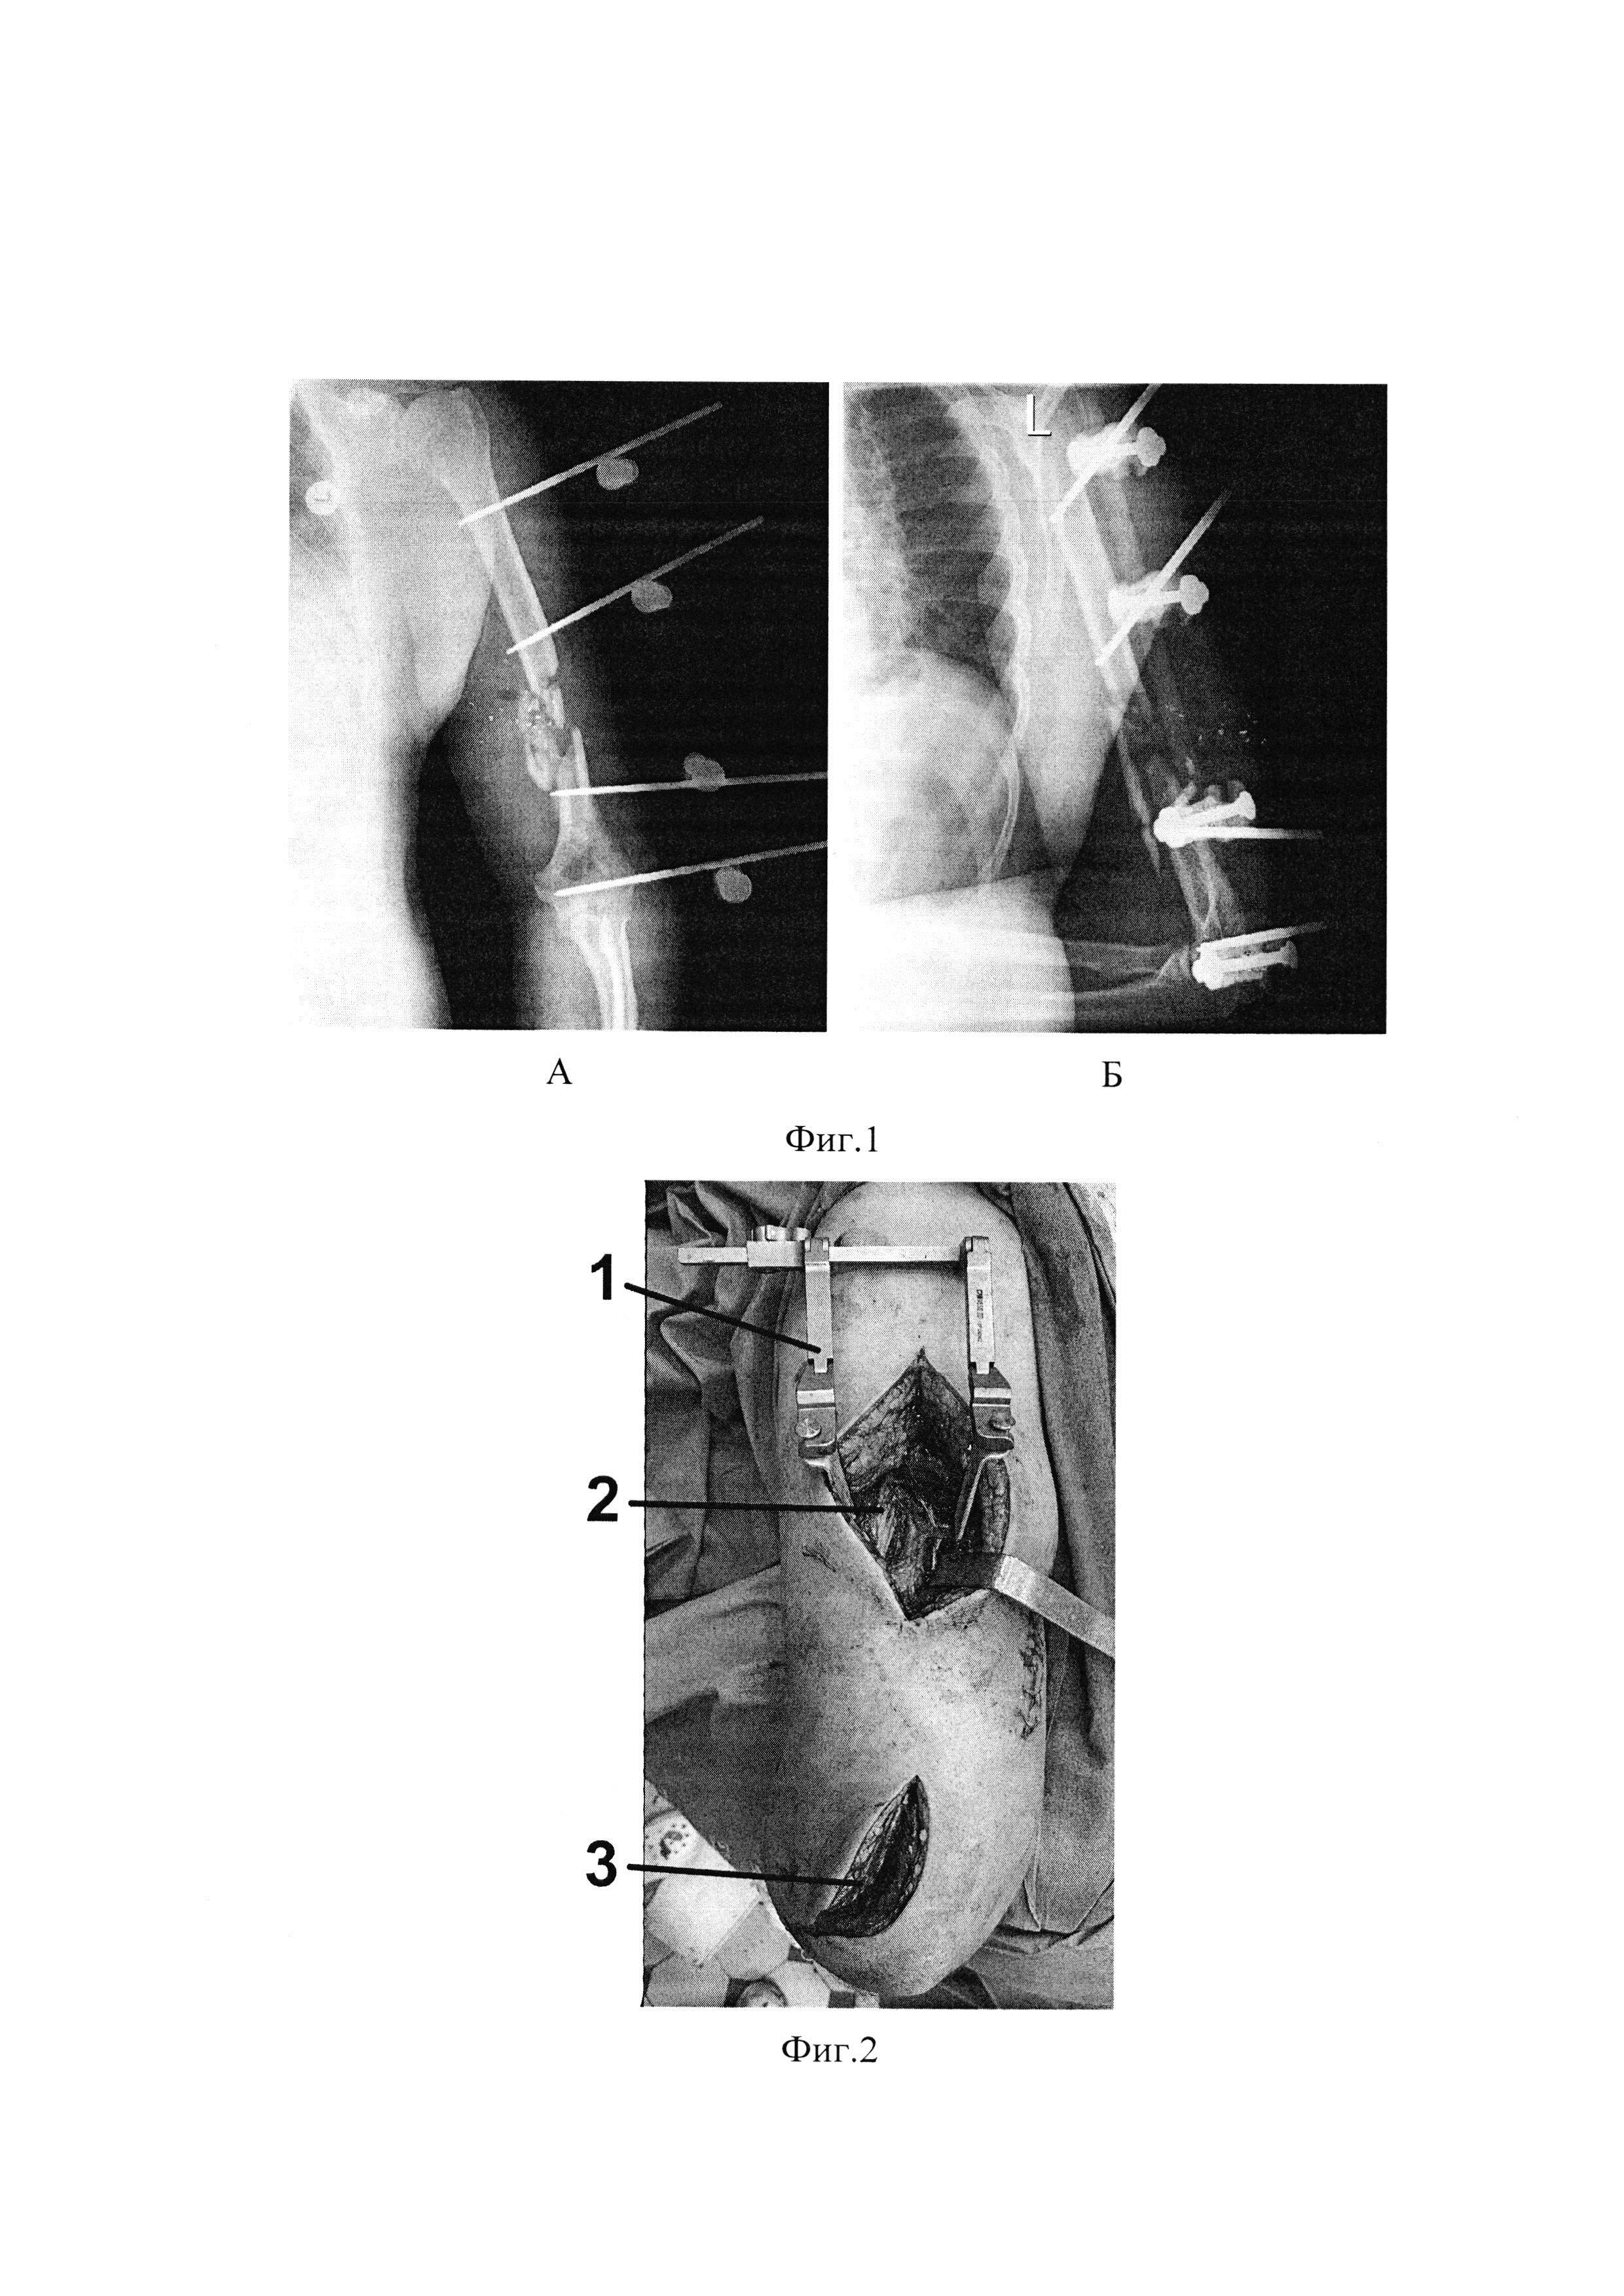

[15]

Фиг. 4. Рентгенограмма левого плеча на 1-е сутки после операции, на которой плечевая кость фиксирована пластиной с угловой стабильностью винтов, при этом проксимальный отломок фиксирован 3-мя винтами, а дистальный - 5-мя винтами. Проксимальный конец пластины прилежит к задней поверхности верхней трети диафиза, дистальный конец - к задней поверхности наружного мыщелка плечевой кости.

Способ последовательного минимально-инвазивного остеосинтеза плечевой кости в нижней трети пластиной при огнестрельных переломах выполняем в несколько последовательных этапа. Положение пациента на здоровом боку, поврежденную верхнюю конечность укладываем на приставку или валик, при этом предплечье устанавливаем в среднее положение между супинацией и пронацией. Первым этапом выполняем проксимальный доступ через трехглавую мышцу плеча 2 длиной 8 см до задней поверхности средней трети плечевой кости (фиг. 2). При этом, в процессе выполнения доступа выполняем визуализацию и мобилизацию лучевого нерва из спирального канала, при необходимости, невролиз. Вторым этапом выполняем доступ в нижней трети плечевой кости по задне-наружному краю плеча и на 1,5-2 см проксимальнее наружного мыщелка 3 длиной 5 см (фиг. 2). Рассекаем трехглавую мышцу плеча по ходу мышечных волокон до наружного мыщелка плечевой кости. Следующим этапом вводим пластину с угловой стабильностью винтов в сформированном подмышечном тоннеле, скользя по задней поверхности плечевой кости (фиг. 3). При этом направитель сверла для винтов с угловой стабильностью вводят в одно из отверстий и используют его как рукоятку. Затем ассистент под контролем ЭОП выполняет закрытую репозицию костных отломков плечевой кости, а хирург, при этом, аккуратно продолжает вводить пластину эпипериостально, проходя снизу-вверх над зоной перелома. Через дистальный доступ на плече дистальный край пластины укладываем по задней поверхности наружного мыщелка. Далее проксимальный конец пластины временно фиксируем к диафизу плечевой кости спицей Киршнера. Под контролем ЭОП окончательно выполняем закрытую репозицию костных отломков плечевой кости (ось, длину и ротацию) и дистальный конец пластины, корректно сориентированной на наружном мыщелке плечевой кости, фиксируем винтами. Производим фиксацию проксимального конца пластины к плечевой кости винтами с угловой стабильностью, (фиг. 4). В области хирургических доступов устанавливаем дренаж. Послойно ушиваем операционные раны.

На одном из этапах медицинской эвакуации пострадавшему выполнена операция: первичная хирургическая обработка ран левого плеча, фиксация левого плеча аппаратом КСВП (фиг. 1 А, Б). Через 2 суток после ранения пациент доставлен в клинику военной травматологии и ортопедии ВМедА. При обследовании выявлено огнестрельное осколочное сквозное ранение левого плеча с огнестрельным многооскольчатым переломом плечевой кости в нижней трети со смещением отломков (фиг. 1 А, Б). В клинике раненому ежедневно выполняли перевязки ран правого плеча с мазью левомеколь, получал комплексное консервативное лечение, а именно: антибактериальную терапию широкого спектра действия, анальгетики. Пострадавшему на 6 сутки после поступления выполнен первично отсроченный шов ран левого плеча. На 18-е сутки после поступления в клинику отмечено заживление огнестрельных ран мягкотканого покрова левого плеча. Через 3 недели от момента ранения выполнена операция: демонтаж аппарата КСВП, закрытая репозиция, минимально-инвазивный остеосинтез левой плечевой кости пластиной с угловой стабильностью винтов (фиг. 3, 4). В послеоперационном периоде на протяжении трех недель проводили иммобилизацию оперированной конечности косыночной повязкой. Активные движения в плечевом и локтевом суставах начинали со вторых-третьих суток после операции по стиханию болевого синдрома.